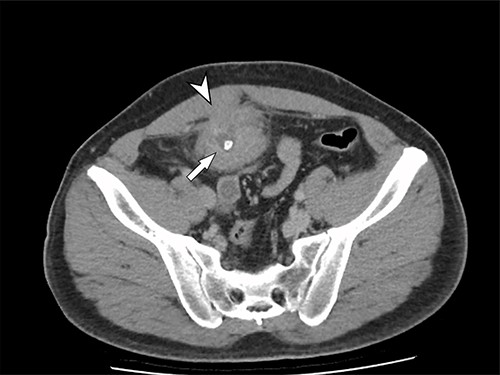

A 41-year-old, previously well, male presented to the emergency department with lower abdominal pain, pyrexia with a temperature of 38.2°C and a palpable suprapubic mass. His relevant background history included an uneventful laparoscopic appendicectomy 2 years prior for acute appendicitis, insulin independent type 2 diabetes and hypertension. He presented with raised inflammatory markers and computed tomography (CT) showing a well circumscribed central pelvis lesion that appeared concerning for a urachal malignancy (Fig. 1). This lesion was closely associated with the dome of the bladder (Fig. 2). This supracystic lesion measured 58 mm × 56 mm with central cystic component of 15 mm in diameter, and contained a 11 mm central calcification. Further characterization with magnetic resonance imaging showed possible extension of this mass to the rectus abdominis without significant lymphadenopathy (Fig. 3). Flexible cystoscopy only found inflammation at the dome. As urachal malignancy could not be unequivocally excluded on imaging studies alone, following multidisciplinary discussion, the decision was made to perform an excision of this lesion.

Axial CT image of the pelvic lesion. Arrow indicates central calcification. Arrowhead indicates involvement of anterior abdominal wall.